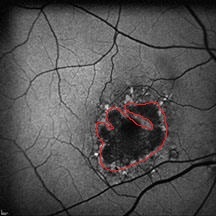

Hypo-angiogenesis: A possible pathological factor in the development of dry age-related macular degeneration and a novel therapeutic target

Background: Angiogenesis causes severe vision loss in patients with exudative or wet forms of age-related macular degeneration (AMD). The pathogenesis involves upregulation of several proangiogenic factors, particularly the vascular endothelial growth factor (VEGF). Contrary to the pathogenesis of exudative AMD, molecular events leading to the development of dry AMD remain unclear. Dry AMD is characterized by loss of the retinal pigment epithelium (RPE). The mechanism that triggers RPE cell loss remains unclear. Choriocapillaris development is absent in mice with RPE-specific deletion of VEGF. Moreover, in later life, background VEGF secretion promotes the survival of the RPE and maintains choriocapillaris integrity.

Hypothesis: We hypothesized that reduced synthesis of VEGF (hypo-angiogenesis) or abnormalities in its receptors, VEGF receptor-1 (VEGFR1) and VEGFR2, may be involved in the pathogenesis of non-exudative AMD or dry AMD. If the concept of hypo-angiogenesis as a driver for dry AMD is proven, treatment with VEGF or induction of angiogenesis could be considered. Similar attempts at therapeutic angiogenesis have been actively investigated in cardiac and limb ischemia.

Conclusions: The reasons for a patient developing exudative AMD or dry AMD remain poorly understood. Nevertheless, targeting increased VEGF production in patients with exudative AMD using anti-VEGF drugs is highly efficacious in preserving vision. Similarly, dry AMD may be a manifestation of reduced VEGF synthesis (hypo-angiogenesis) and subsequent decreased RPE cell survival. Experimental studies exploring the possibility of reduced VEGF secretion and/or increased receptor resistance/abnormality could pave the way for clinical trials of angiogenesis to treat dry AMD.